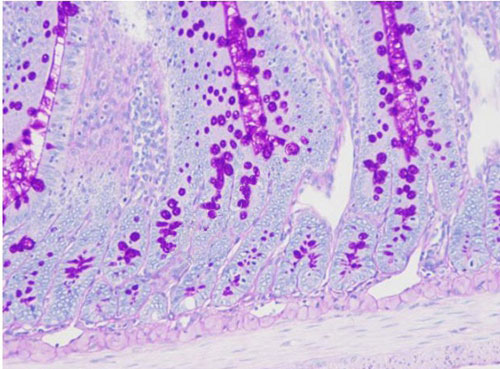

PAS染色又稱過碘酸雪夫染色,糖原染色。一般用來顯示糖元和其它多糖物質。過碘酸能使細胞內的多糖乙二醇基氧化成二醛,再與Schiff氏液的無色品紅結合,紅色,定位于胞漿上

PAS染色—小鼠腸

糖原、中性粘液物質、軟骨基質、植物的真菌和細胞壁、上皮的基膜等均呈紫紅色,細胞核淺藍色